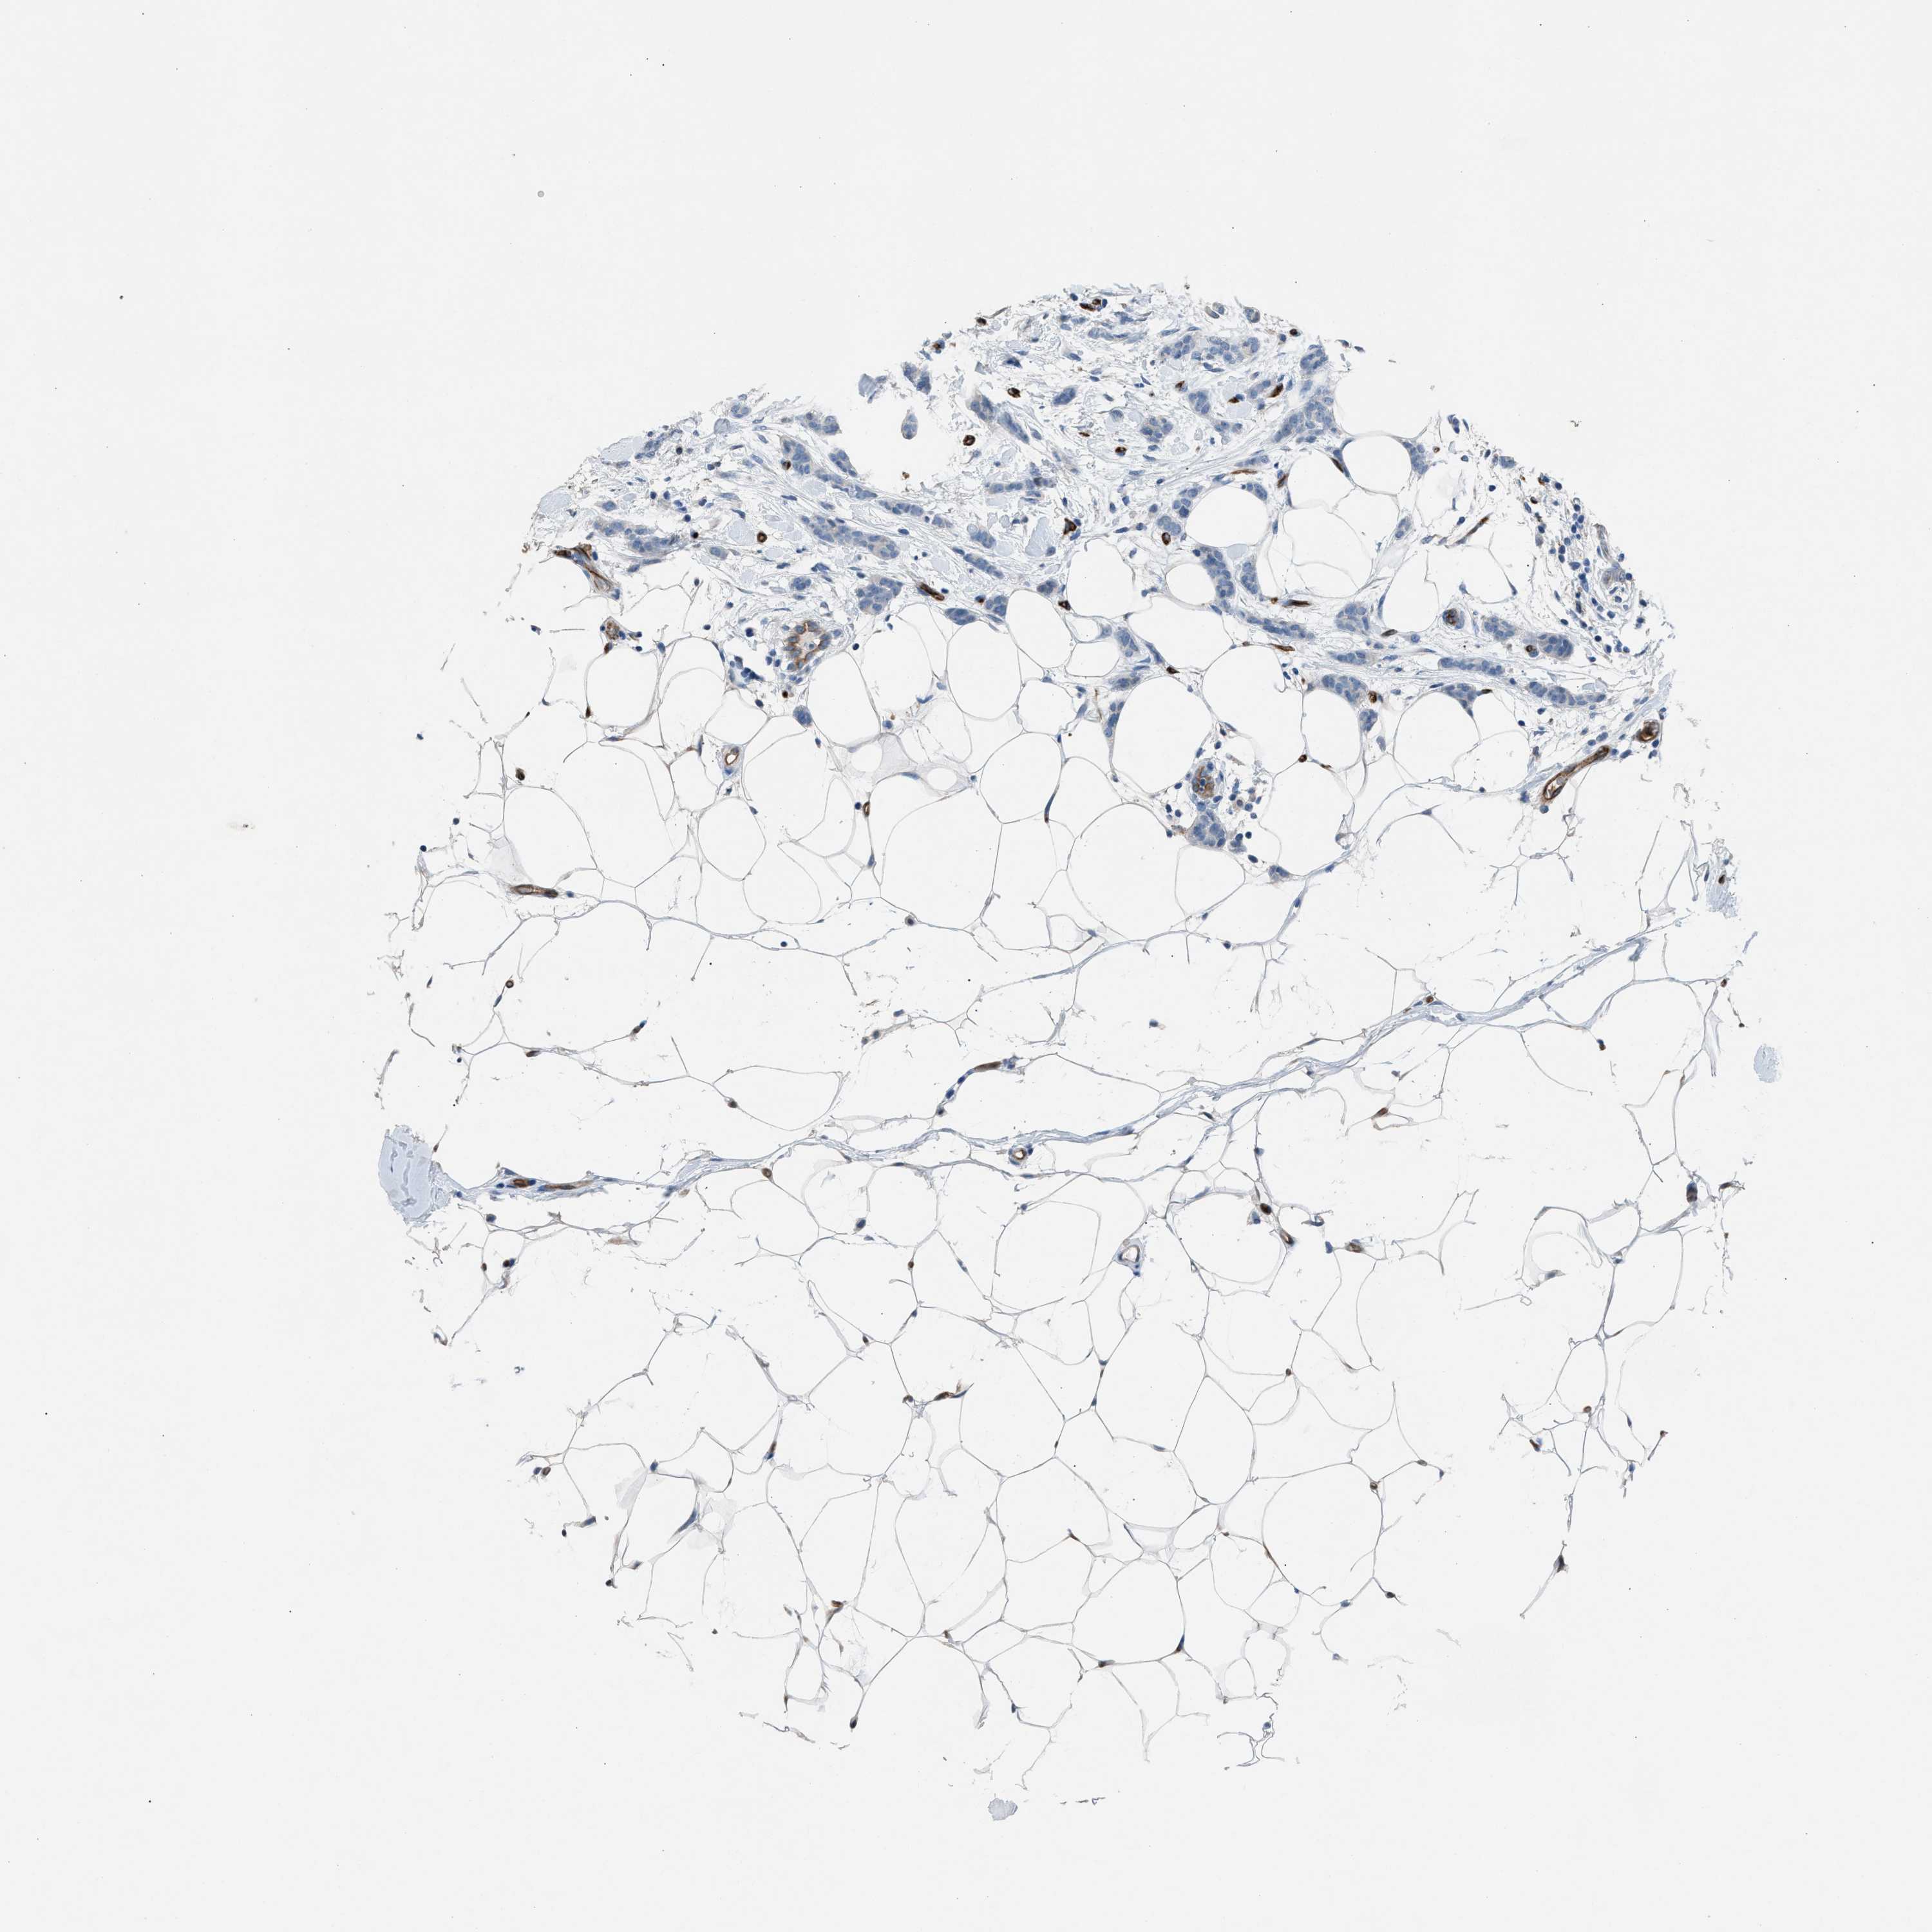

CANCER BREAST CANCER Show tissue menu

Breast cancer

Human cancer